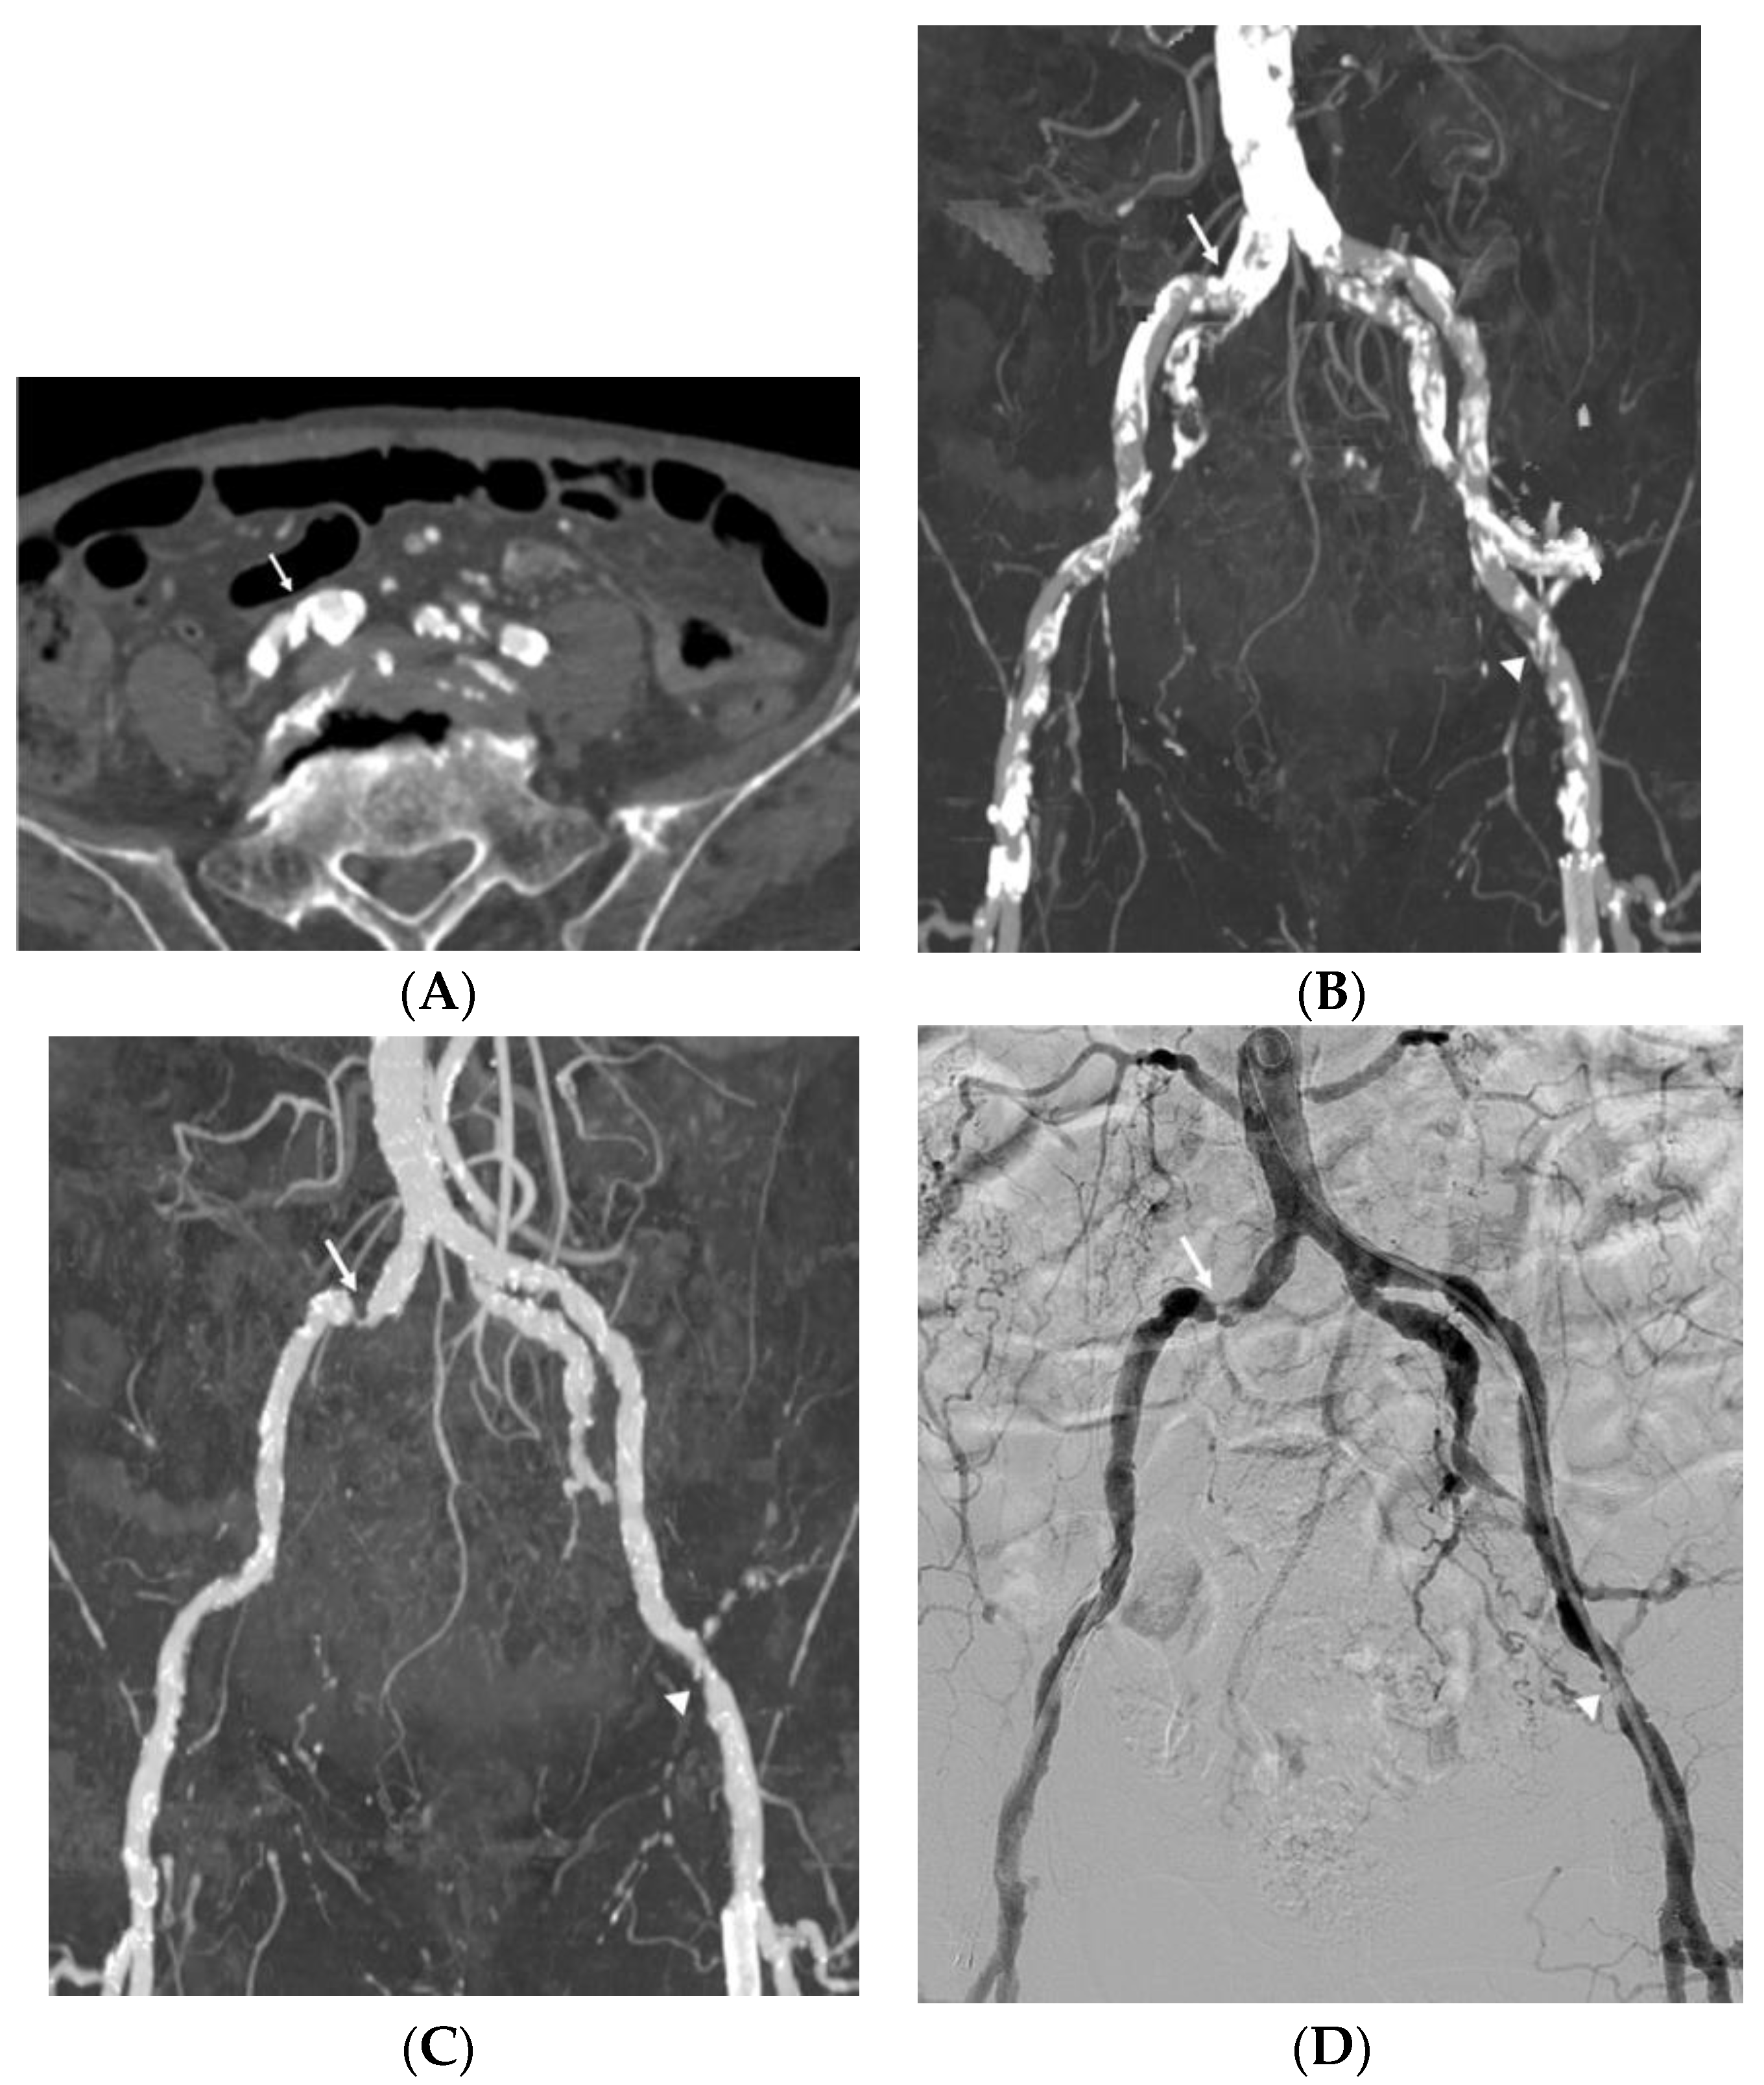

3.3. Impact of Vascular Wall Calcification